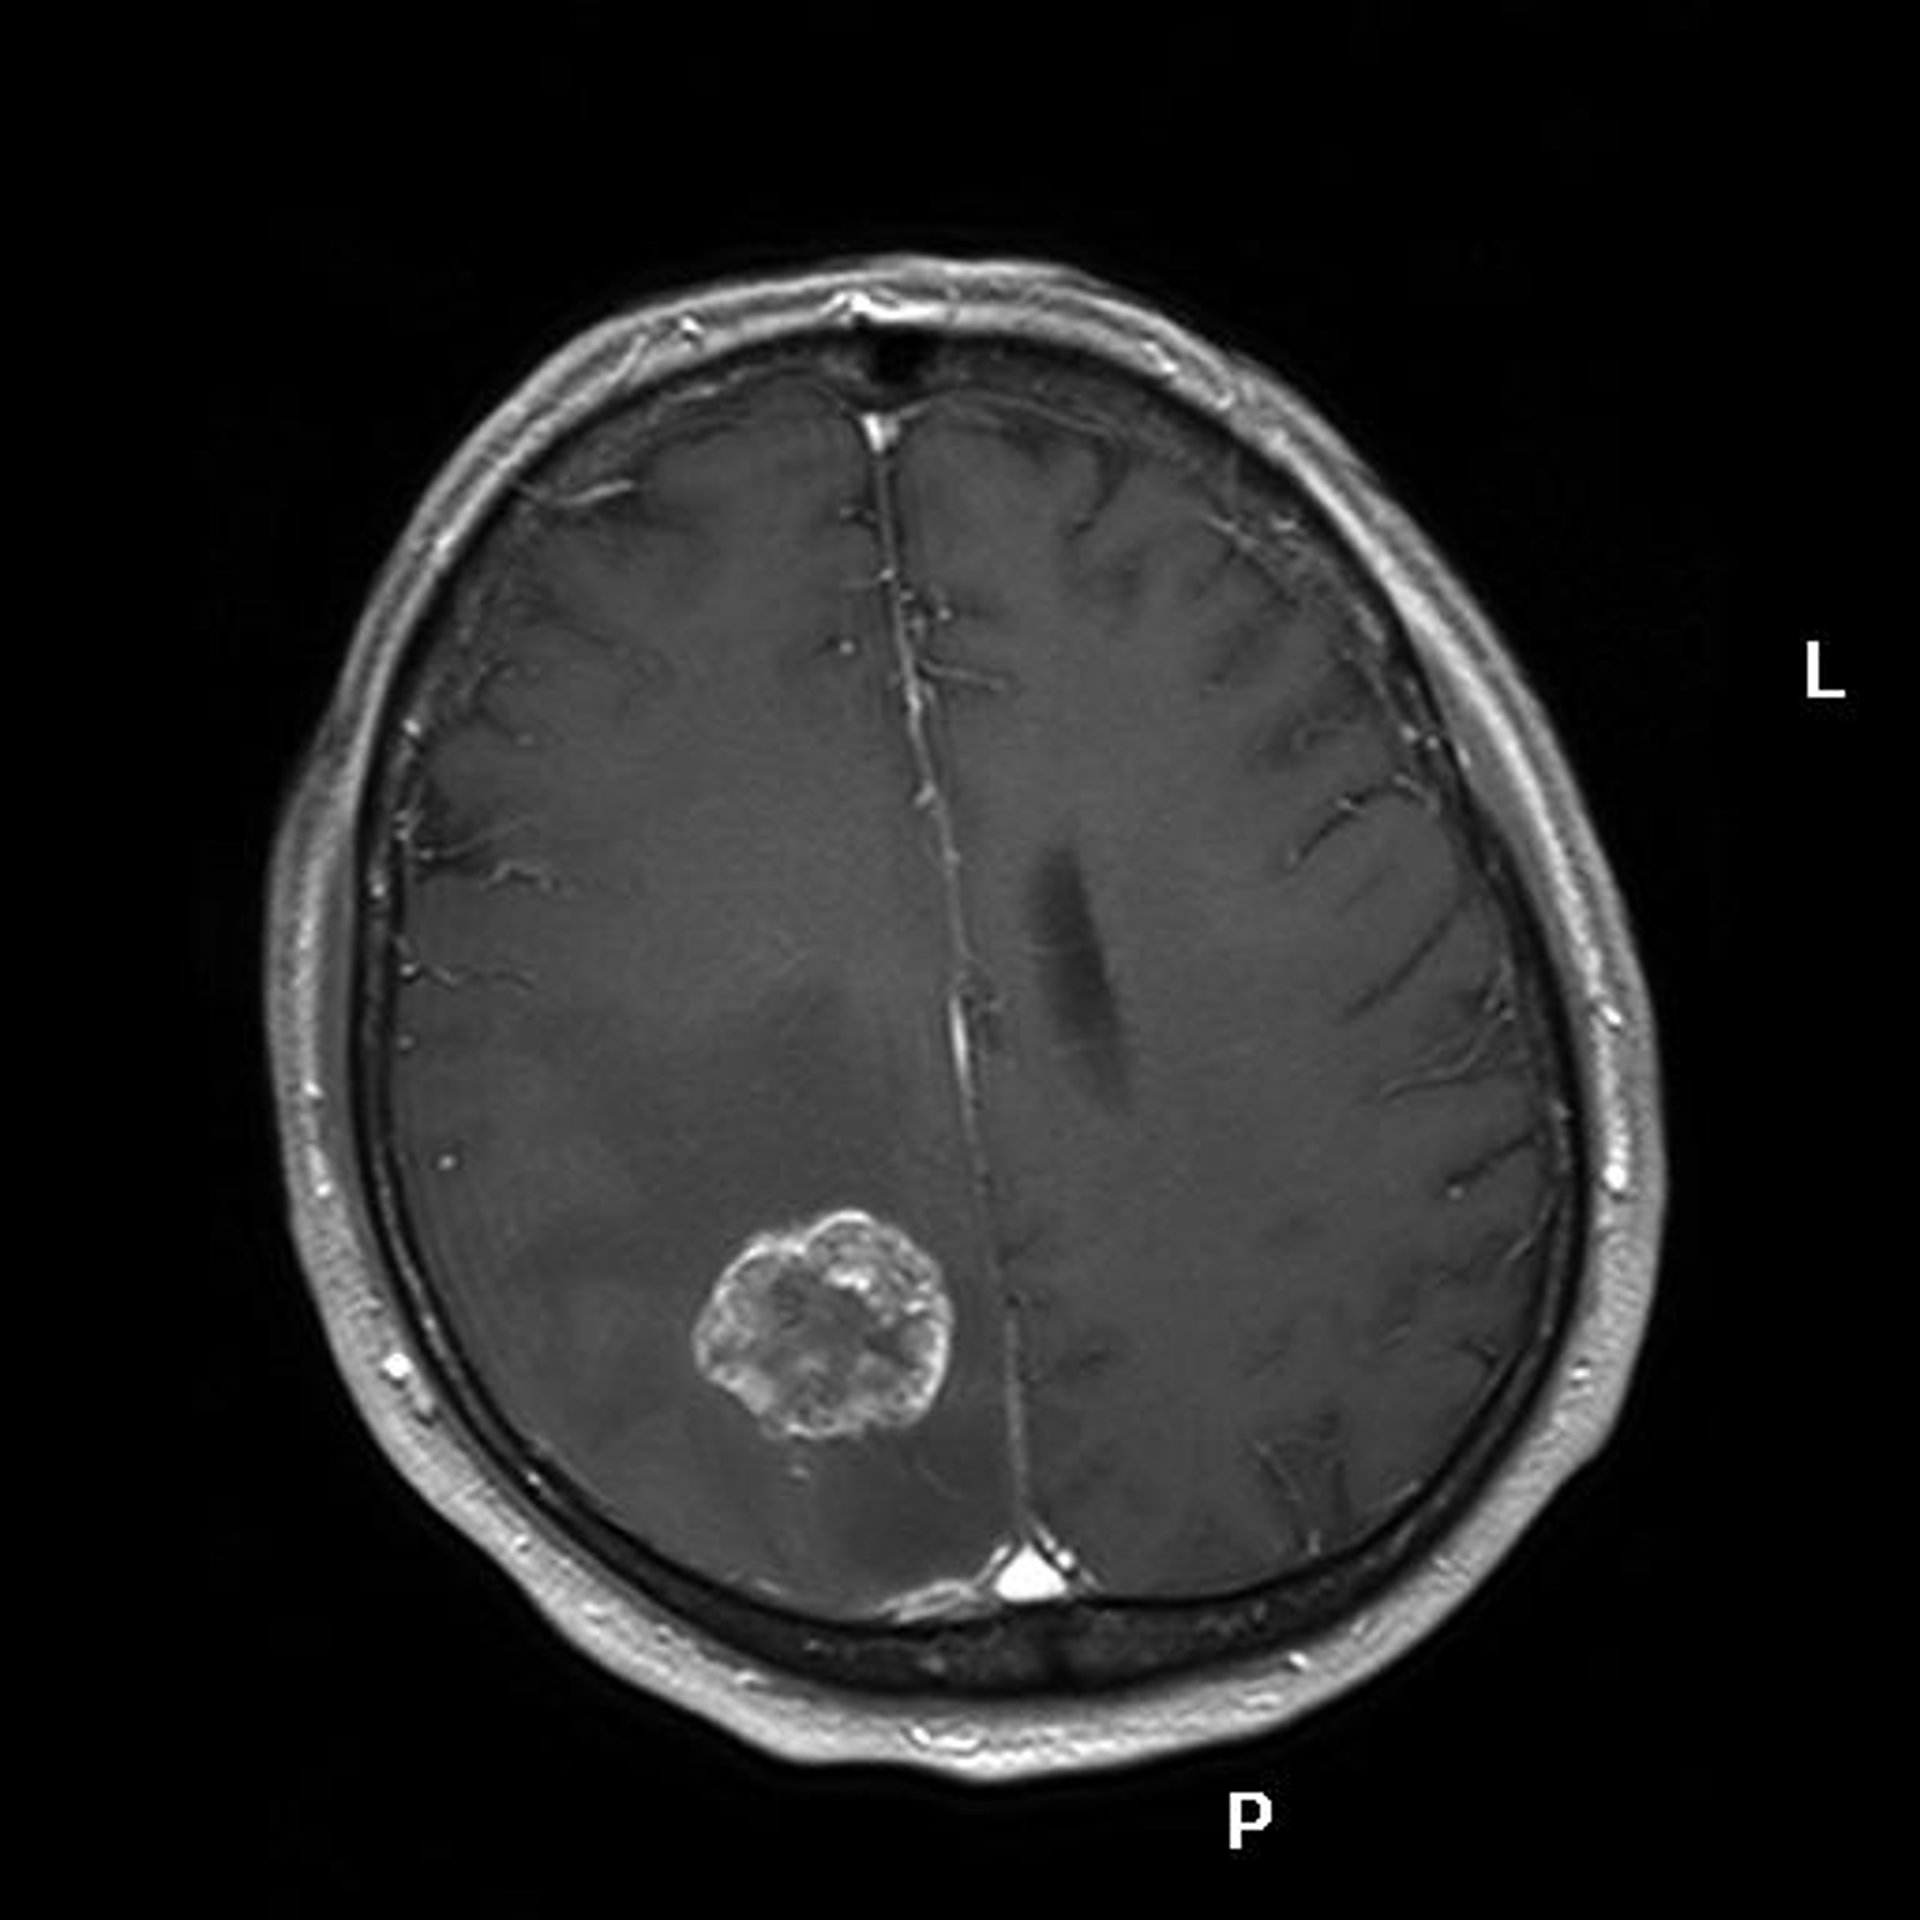

Identifican un subtipo de cáncer cerebral con mejor pronóstico

Cáncer, Tumor, Metástasis

Investigadores de la Universidad de California del Sur en Los Ángeles (Estados Unidos) han descubierto que alrededor del 10 por ciento de pacientes con glioblastoma multiforme, un agresivo cáncer cerebral, presentan un perfil genético diferente.

El estudio, que se publica en la edición digital de la revista 'Cancer Cell', podría conducir a un mejor conocimiento de la progresión clínica de algunos pacientes con este agresivo tipo de cáncer cerebral y abrir la vía a tratamientos más específicos.

Según explica Peter W. Laird, director del estudio, "la mayoría de pacientes sobrevive menos de 15 meses y menos del 10 por ciento viven más de cinco años. Con esta investigación hemos identificado un subgrupo de pacientes con un tipo diferente de glioblastoma multiforme que tiene una mejor progresión clínica y una supervivencia media de más de tres años a partir del diagnóstico".

El perfil epigenético característico descubierto por los investigadores se denomina 'fenotipo metilador de la isla CpG de glioma' (G-CIMP, según sus siglas en inglés) y se descubrió en pacientes mucho más jóvenes. Los tumores G-CIMP tienen alteraciones distintivas en su perfil genómico, lo que revela una asociación con una mutación adquirida en el gen IDH1.